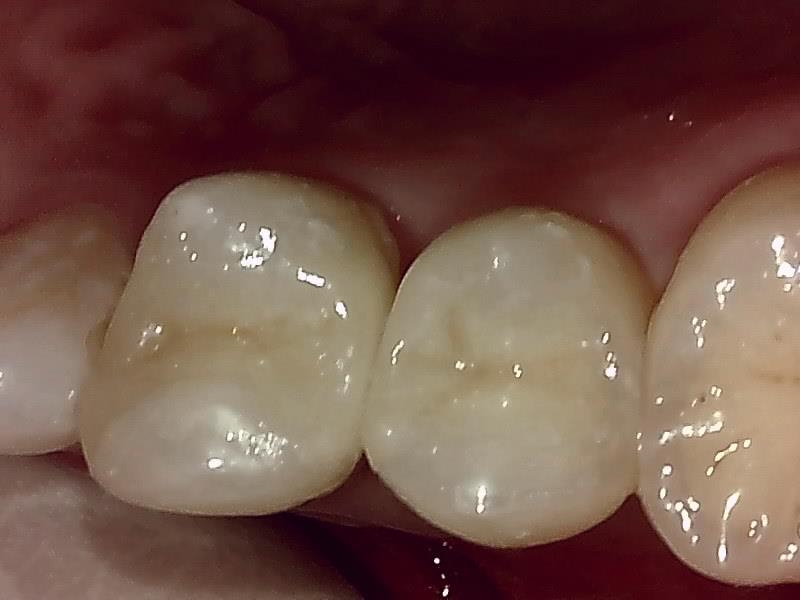

写真; セラミックインレー装着後の歯冠の仕上がり(咬合面観)